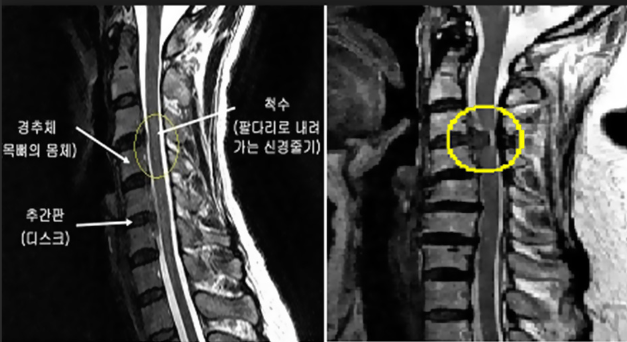

목의 해부학 구조

목, 즉 경추는 머리의 무게를 지탱할 뿐만 아니라 놀라운 가동 범위를 제공하는 복잡한 구조입니다. 목의 해부학적 구조를 이해하려면 이 중요한 부위를 구성하는 척추뼈, 추간판, 근육, 인대, 신경 및 혈관을 깊이 파고드는 것이 필요합니다.

목 해부학의 핵심에는 C1부터 C7까지 지정된 7개의 뼈가 서로 쌓여 있는 경추가 있습니다. 이 척추뼈는 목의 기능을 수용할 수 있도록 독특하게 구성되어 있습니다.

추간판은 각 척추체 쌍(C1과 C2 사이 제외) 사이에 위치하며 충격 흡수 장치 역할을 하고 척추에 유연성을 제공합니다. 각 디스크는 섬유테라고 불리는 질기고 섬유질의 외층으로 구성되어 있으며, 이는 속질핵으로 알려진 더 부드럽고 젤 같은 중심을 둘러싸고 있습니다.